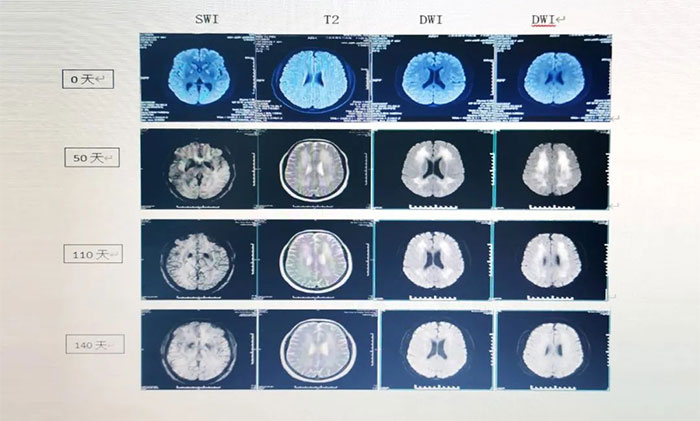

▲ 新冠后急性壞死行腦病患者影像變化

張靜波主任說,ANE發(fā)病機制并不十分清楚,國際上比較公認(rèn)的是細(xì)胞因子增高導(dǎo)致大腦繼發(fā)性損害,如果能積極控制細(xì)胞因子水平,將有望改善預(yù)后,關(guān)鍵在于在神經(jīng)系統(tǒng)損壞不可逆之前,及時發(fā)現(xiàn)細(xì)胞因子增高,從而進(jìn)行抗細(xì)胞因子藥物治療干預(yù)。

張靜波主任分享的病例,以其完整的時間鏈,詳實的研究數(shù)據(jù),規(guī)范、及時、精準(zhǔn)化的治療方案,使患者從完全臥床、癡呆狀態(tài),到痊愈,得到與會專家的高度評價。